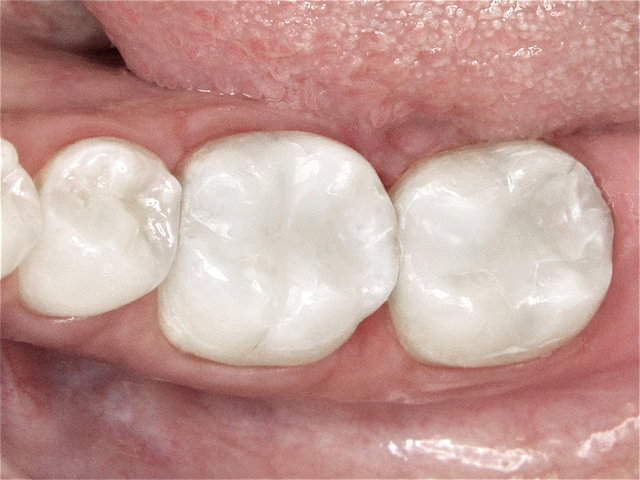

Alte Amalgam-Füllungen mit Sekundärkaries ...

Composit-Füllungen by CLINICDENT ✓